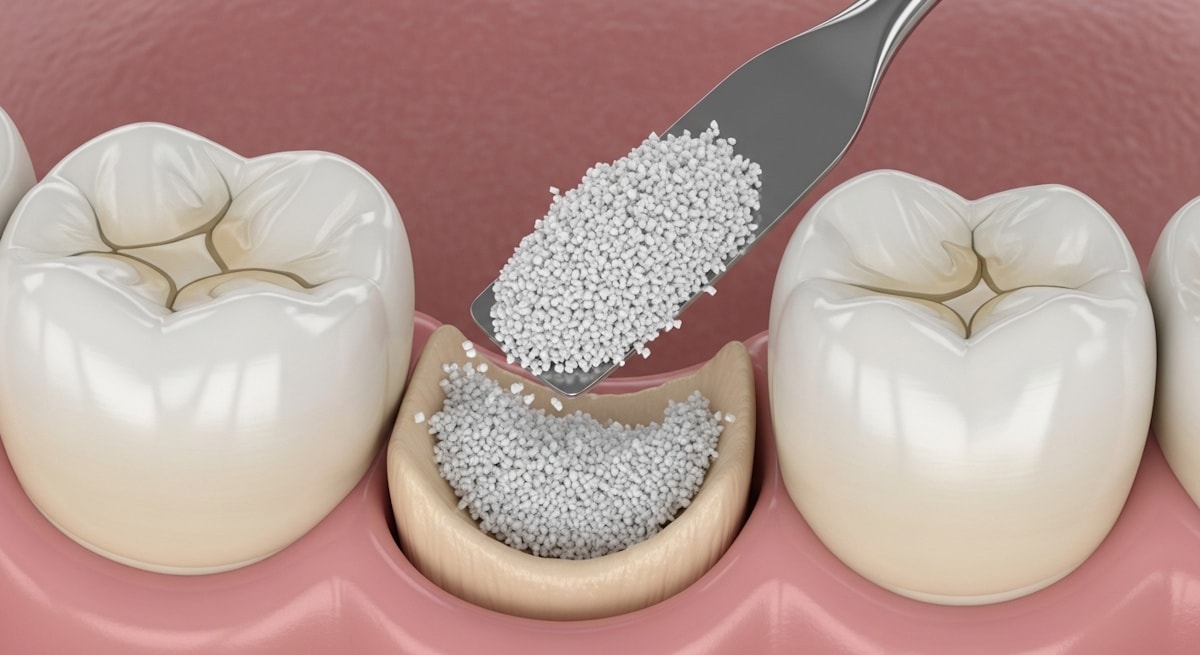

When You Need a Bone Graft

Sometimes you will need a dental bone graft for tooth implant. Bone grafting promotes new bone growth. It also prevents bone resorption and collapse of the ridge.

When successful, you’ll have enough bone width for a successful implant placement.

Bone Grafting for Tooth implants in Alexandria, VA